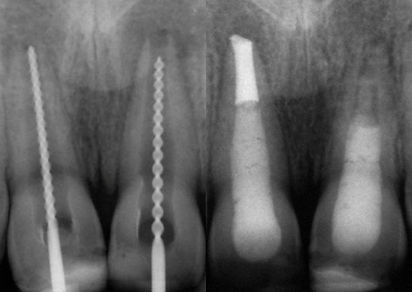

Pan Sławomir został skierowany z innego gabinetu w celu usunięcia z kanału bardzo długiego fragmentu złamanego narzędzia.

Dzięki dużemu doświadczeniu i użyciu specjalistycznych narzędzi oraz powiększenia w mikroskopie dr Agnieszka Żęcin usunęła złamane narzędzie.

Pacjent uniknął usunięcia zęba, a wizyty kontrolne potwierdzają, że ząb przez wiele lat pozostaje bezobjawowy i pełni swoją funkcję.